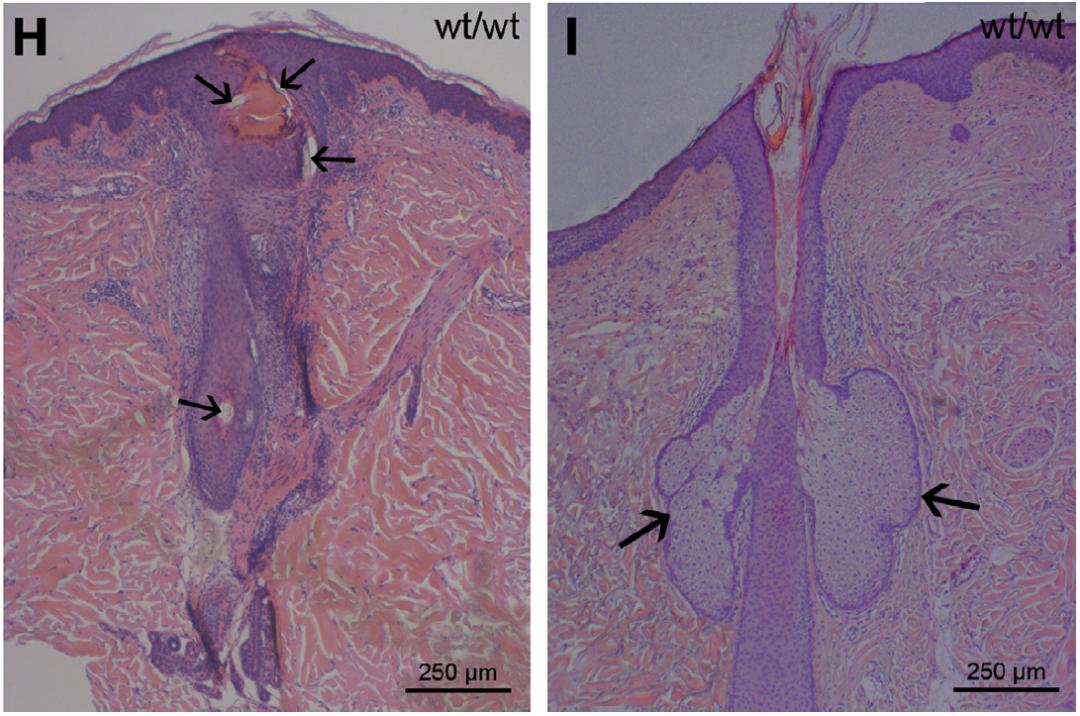

毛周角化病的形成与一种蛋白质——角蛋白有关。角蛋白能起到保护上皮细胞免受有害物质损伤和感染的作用。当它聚集起来,毛囊开口就会被堵住,导致皮肤出现凹凸不平的丘疹。角蛋白聚集的原因可能与丝聚蛋白突变相关,大多数的毛周角化病遗传模式符合不完全外显的常染色体显性遗传。